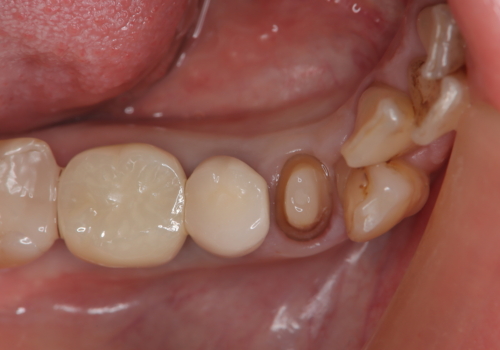

- フロスをしていたが歯と歯の間にはさまり、取れなくなったとのご相談にいらした患者様です。以前、他院で治療した部分に凹みがあり、その部分にフロスが残留しちぎれていました。このため、根本的に歯のかぶせ物・詰め物を新しくする必要があると判断いたしました。治療後はフロスでのケアもスムーズになり、良好な経過をたどっています。